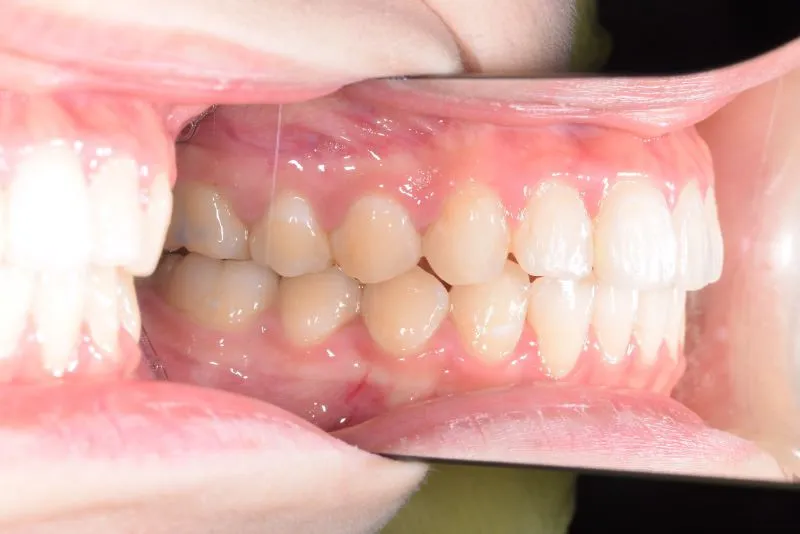

• 初診時

初診時

初診時年齢 19~29歳 (女性) 主訴 上下がガタガタ・出っ歯

診断名 叢生・上下顎前突 装置名

上下の歯並びがガタガタで口元が出ています。

元々小学生の時にマルチブラケット装置を上下につけ、矯正治療を受けていました。

何年か経過後、ガタガタと口元が気になると受診されました。

再治療の時は、上の歯は前から見えにくいオリジナル固定装置、下の歯はマルチブラケット装置を使用し、治療しました。